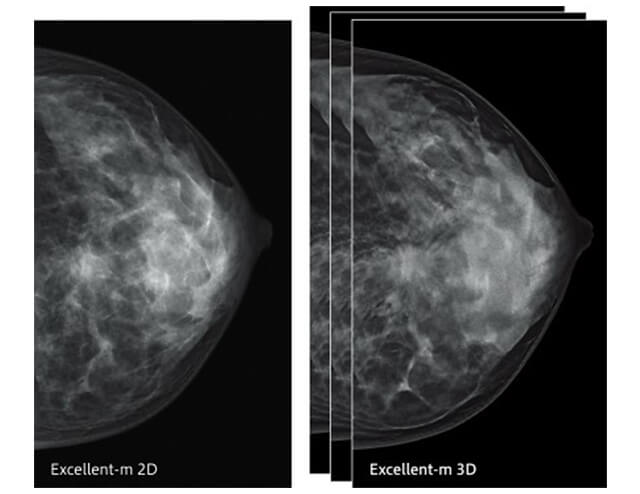

マンモグラフィー部⾨

当センターではマンモグラフィ検査の診断⽤装置として新しくFUJIFILMの「AMULET Innovality」を導⼊しました。この装置ではこれまでより低線量で⾼画質な画像の提供が可能となり、検査に来られる患者さんの負担をできるかぎり軽減することを考え、充実した検査の向上に努めてまいります。

ここではこの装置の説明として、以下の特徴を紹介します。

新たな機能「トモシンセシス」

マンモグラフィ検査では、通常誰にでも⾒られる乳腺は診断⽤画像で⽩く写ってしまい、特に⾼濃度乳腺のような⽅の場合であると、この乳腺の中に疾患が隠れてしまうことがあります。検査時には乳腺に隠れるくらいに⼩さく早期の腫瘍であっても、約100⽇〜半年ほどで倍の⼤きさになると⾔われており、早期発⾒へと繋げるためにはいかにこの⼩さな腫瘍を発⾒できるかにかかっています。そこでこの度新たに加わる機能としてトモシンセシスを⾏えるようになりました。X線管球が胸の上を連続的に移動し、複数の画像を重ね合わせることで、⽴体的な画像を構成し、乳腺との重なり部分等をより詳しく観察できるようになったため、従来の⼆次元の画像では発⾒の難しかった疾患も容易に観察できるようになりました。

⾼画質な画像の提供

画像の観察を⾏ううえで、乳房の中にある⼩さな⽯灰化や腫瘍等をきれいに細かく写すことは⾮常に重要となります。そこで、今回の装置では画像認識技術によって患者さんごとに体内の⽴体構造を捉え、ざらつきの無い画像を提供できるようになりました。

画像認識技術による画像の提供

画像認識技術による画像の提供

低線量での撮影

従来の装置に⽐べて約30%の線量低減が可能となりました。

痛みの軽減

圧迫⾃動減圧制御(なごむね):患者さんの痛みを軽減するため、通常の乳房圧迫完了後に、乳房の厚みが変化しない範囲(±3mm)で圧迫圧を減圧する機能を有します。

以上のことより、検診から精密検査まで、安⼼して患者さんに検査を受けていただけるよう、精度の⾼い画像の提供をしてまいります。